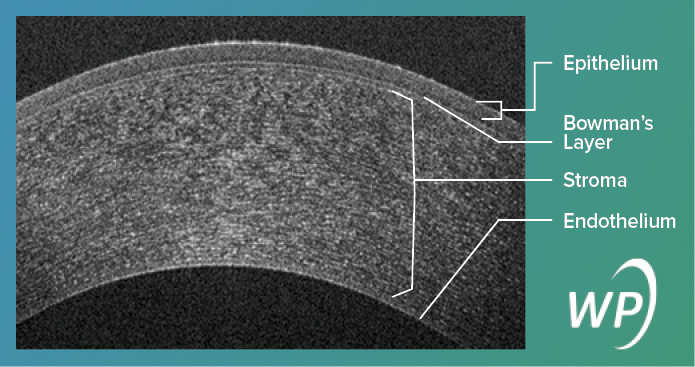

Although 1300 nm OCT is favored for imaging of deeper anterior segment structures, the cornea’s proximity to the surface make it ideal for 800 nm SD-OCT, which offers better resolution. In this image, we’ve used a system designed with our broad bandwidth Cobra-S spectrometer for highest resolution. This makes it possible to clearly see all key corneal layers, beginning with evidence of a thin, bright tear film and the thicker epithelium below, followed by Bowman’s layer. The broad corneal stroma layer dominating the corneal body shows evidence of keratocytes, and is bounded at bottom by a thin endothelium. Let’s take an even closer look – at the microscopic level.